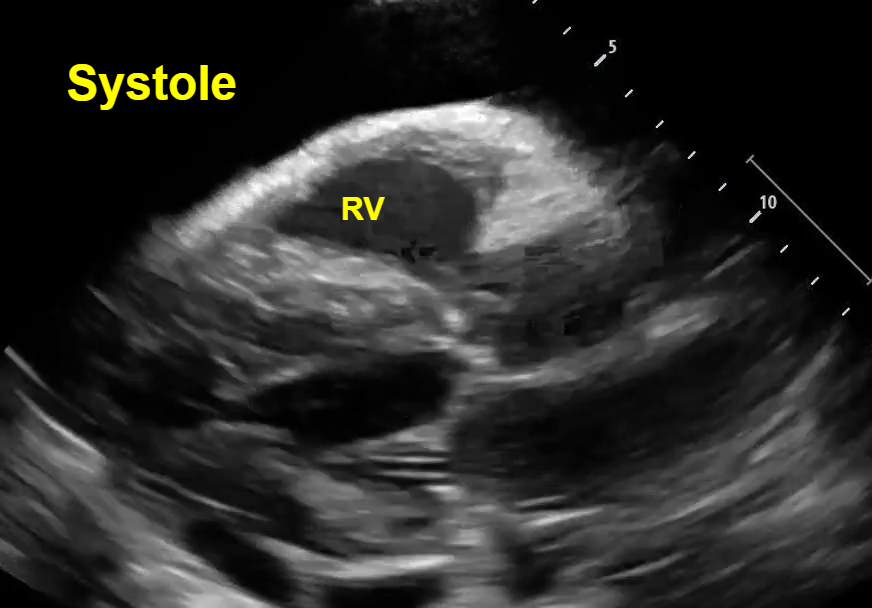

In both parasternal and short axis views seen above, there is a circumferential pericardial effusion surrounding the entire heart.

Short axis view: Here we see an example of ‘trampoline sign’, which is the characteristic bouncing motion of the RV. In the image above, we see inversion of the RV wall during diastole (arrow). How do we know this is diastole? Again, note that we can see the opening of the mitral valve in the LV when the RV wall inverts. See clip #2 to see a video of the ‘trampoline sign’.